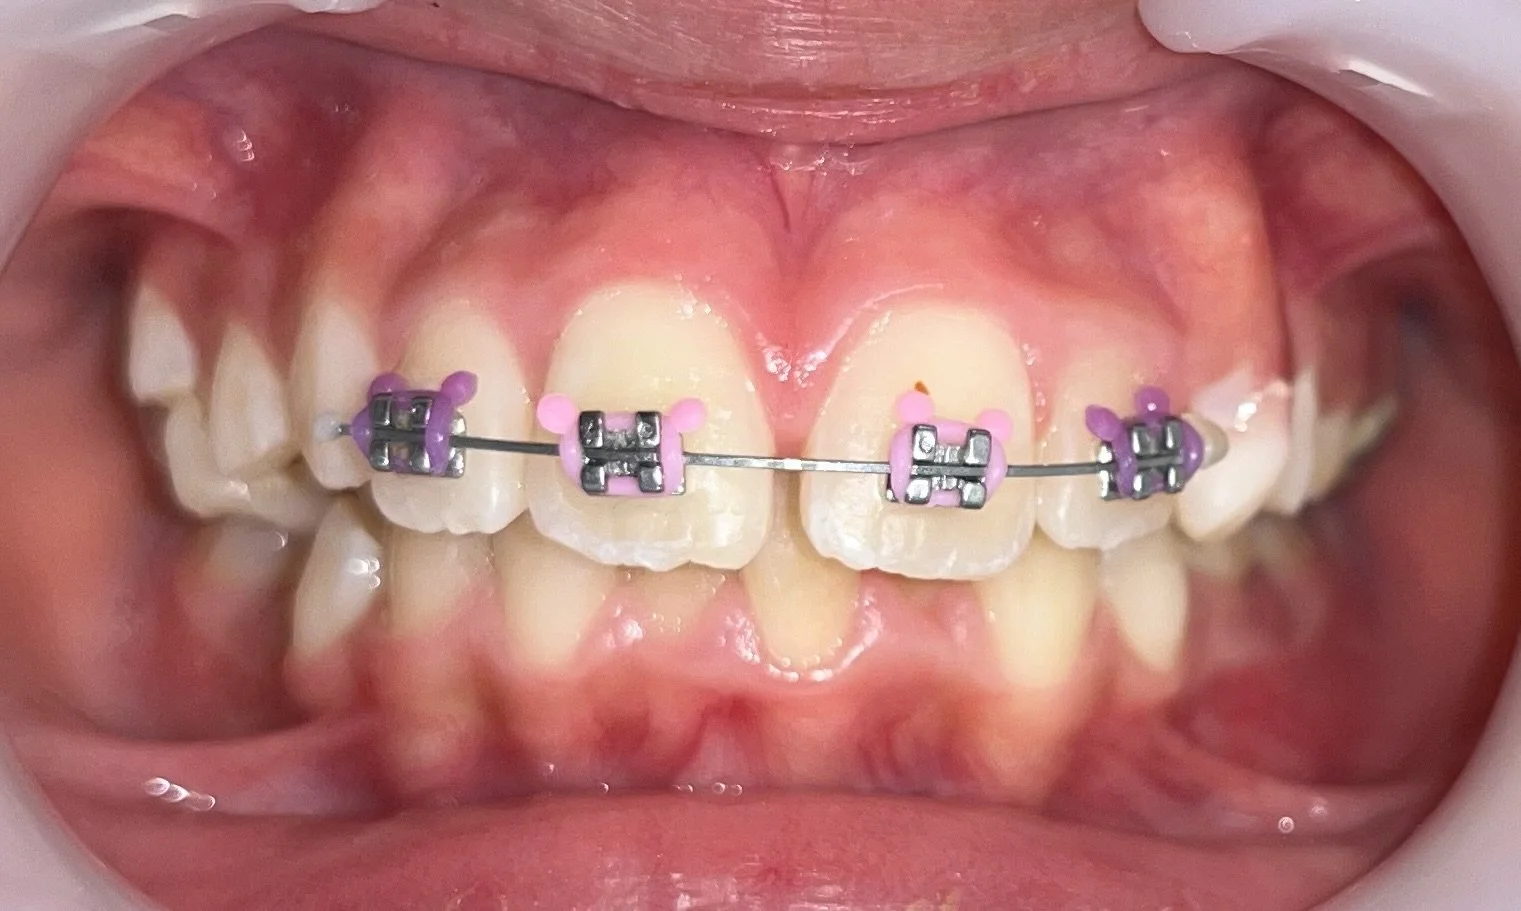

Deuxième phase : l’orthodontie de l’adolescent (11–15 ans)

Lorsque toutes, ou presque toutes, les dents définitives sont en place, la seconde phase permet d’aligner les dents avec précision et d’optimiser la fonction masticatoire. Cette étape vise à obtenir un sourire stable, durable et harmonieux.